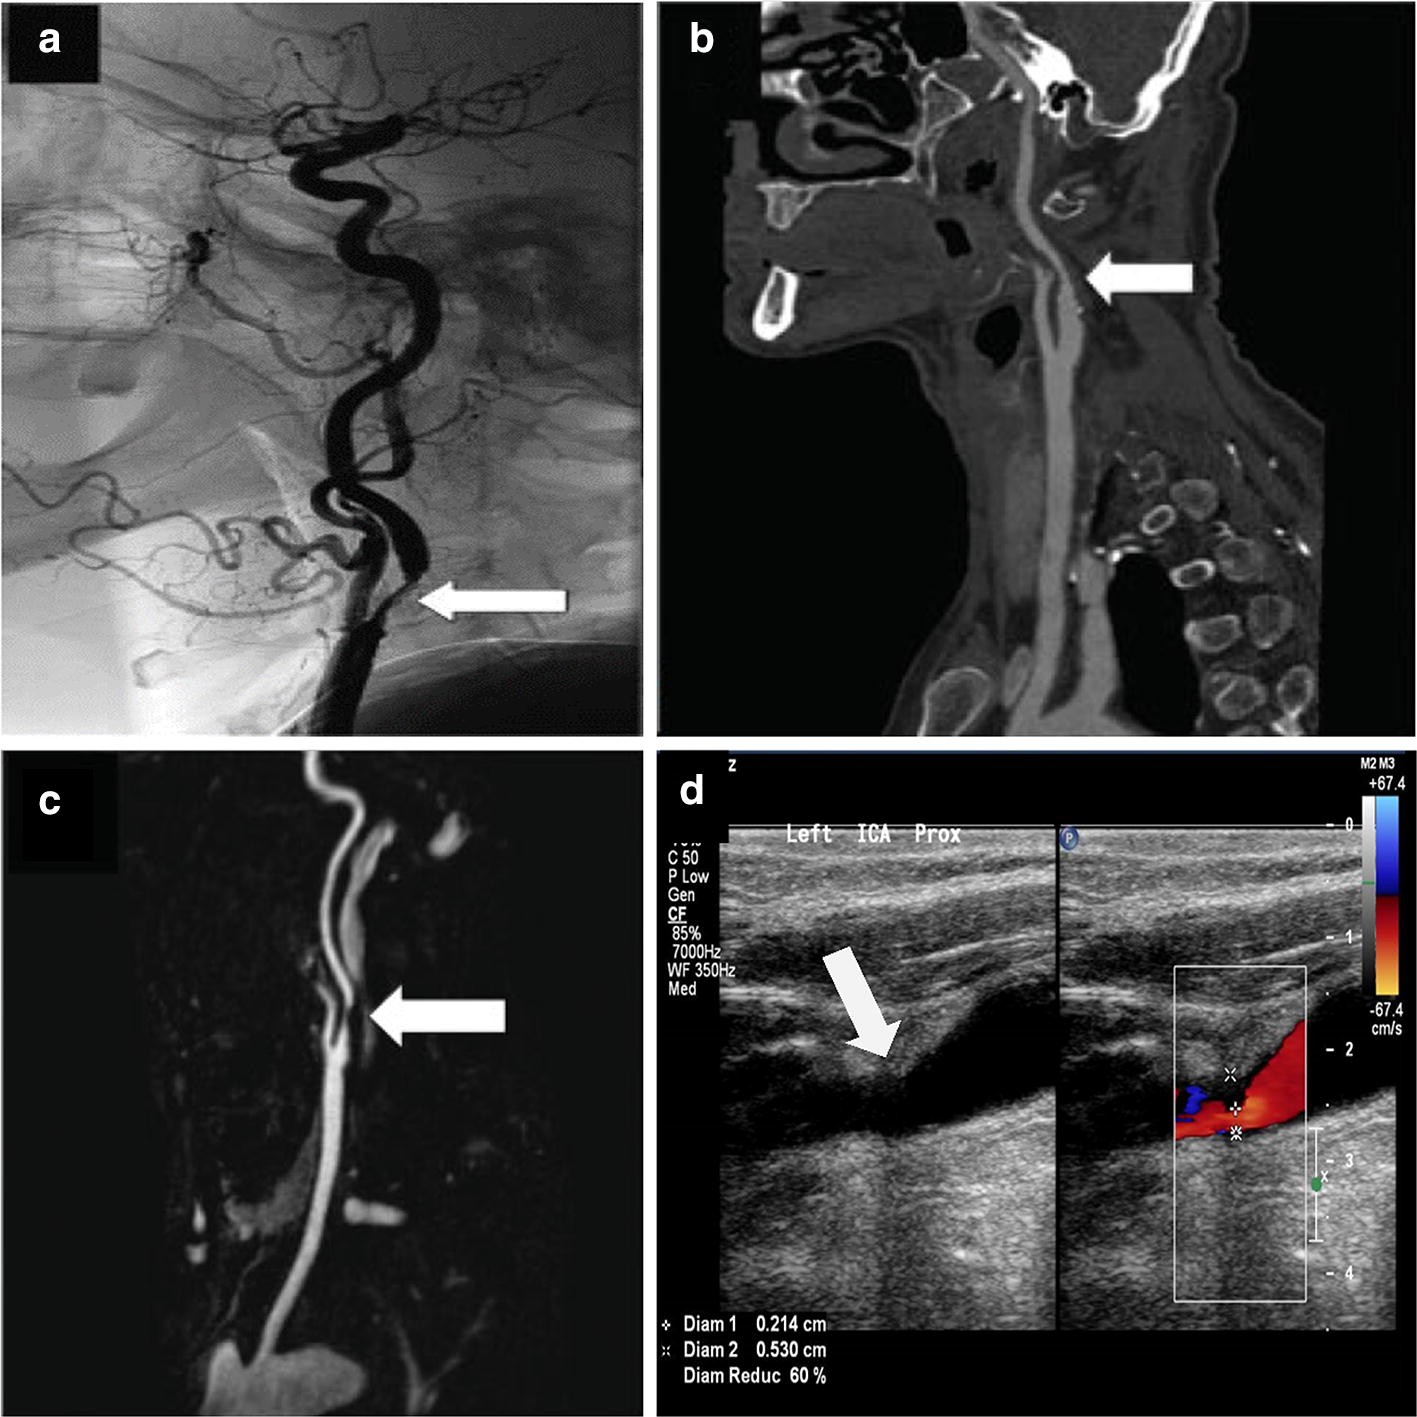

Fig. 10From: Imaging modalities to diagnose carotid artery stenosis: progress and prospectICA stenosis visualization with a white marker arrow in a DSA image [75], b CTA image [75], c MRA image [75], and d DUS image (credits: National Heart Center Singapore)Back to article page